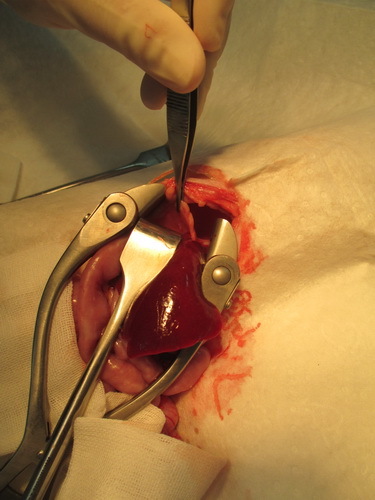

10月15日做手術

10月17日手術成功,小黑帽狀況還不錯

照片3是手術前 照片6是手術後動物近況說明: 小黑帽18號回家,還蠻緊張的,沒有像在醫院那麼穩定,會哈氣,19號有穩定些,慢動作的接近他,就不會呼我了,我有用浴巾包住抱著她幫他測了體重是1.8公斤,目前以皇家幼貓當主食,然後每天會再加一餐【貝克牛磺酸錠磨成粉+THOMAS LABS 湯瑪士離氨酸 拌日本AIXIA《MiawMiaw》金妙喵(肽添加-肉狀餐罐)給他吃,所以他目前會吃到4餐,他目前的食慾都很好,喝水量都有超過150CC,他身上黴菌的部分已有好轉35%,想說等她再胖一點,皮膚狀況好一些再進行送養部分,我有在自己的臉書上寫他的一些生活狀況,請朋友分享讓認養進度可以快一點